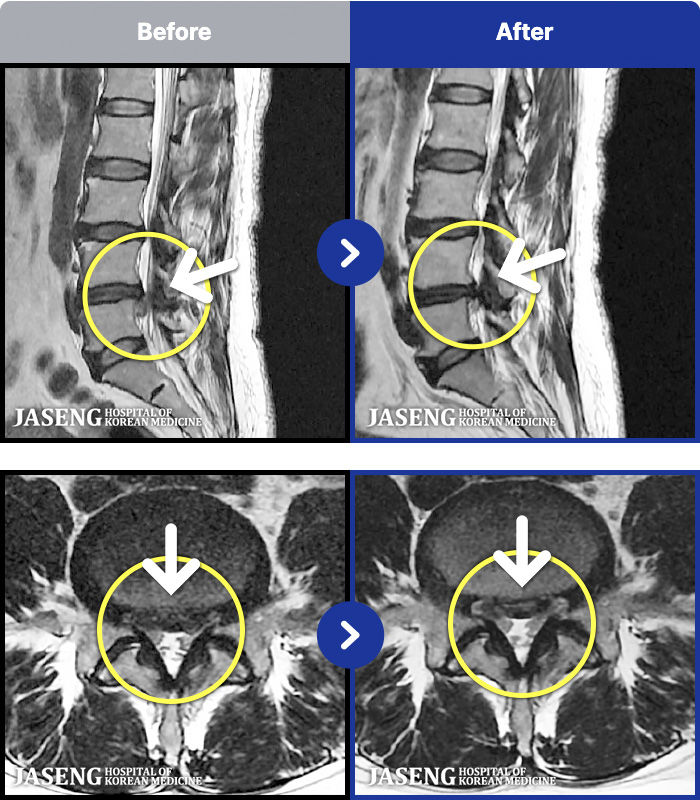

MRI ġ

1,240 MRI ũ ʸ Ȯϼ.